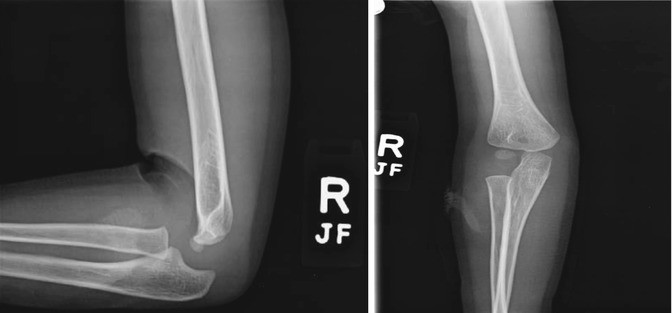

The evaluation of pediatric elbow radiographs in the setting of acute trauma may be challenging for many emergency department physicians, orthopedic surgeons, and radiologists.

Diagnostic difficulties stem both from the complex developmental anatomy of the elbow and from significant differences. Posted by radiologypics ⋅ april 9, 2013 ⋅ leave a comment. The arm also referred to as the upper limb is connected to the chest by the shoulder joint.

At first, the elbow seems like a simple hinge. The evaluation of pediatric elbow radiographs in the setting of acute trauma may be challenging for many emergency department physicians, orthopedic surgeons, and radiologists. The humeroulnar, humeroradial, and proximal radioulnar joints. Along with the necessary skills, anatomy is the key to consistent results in open and.